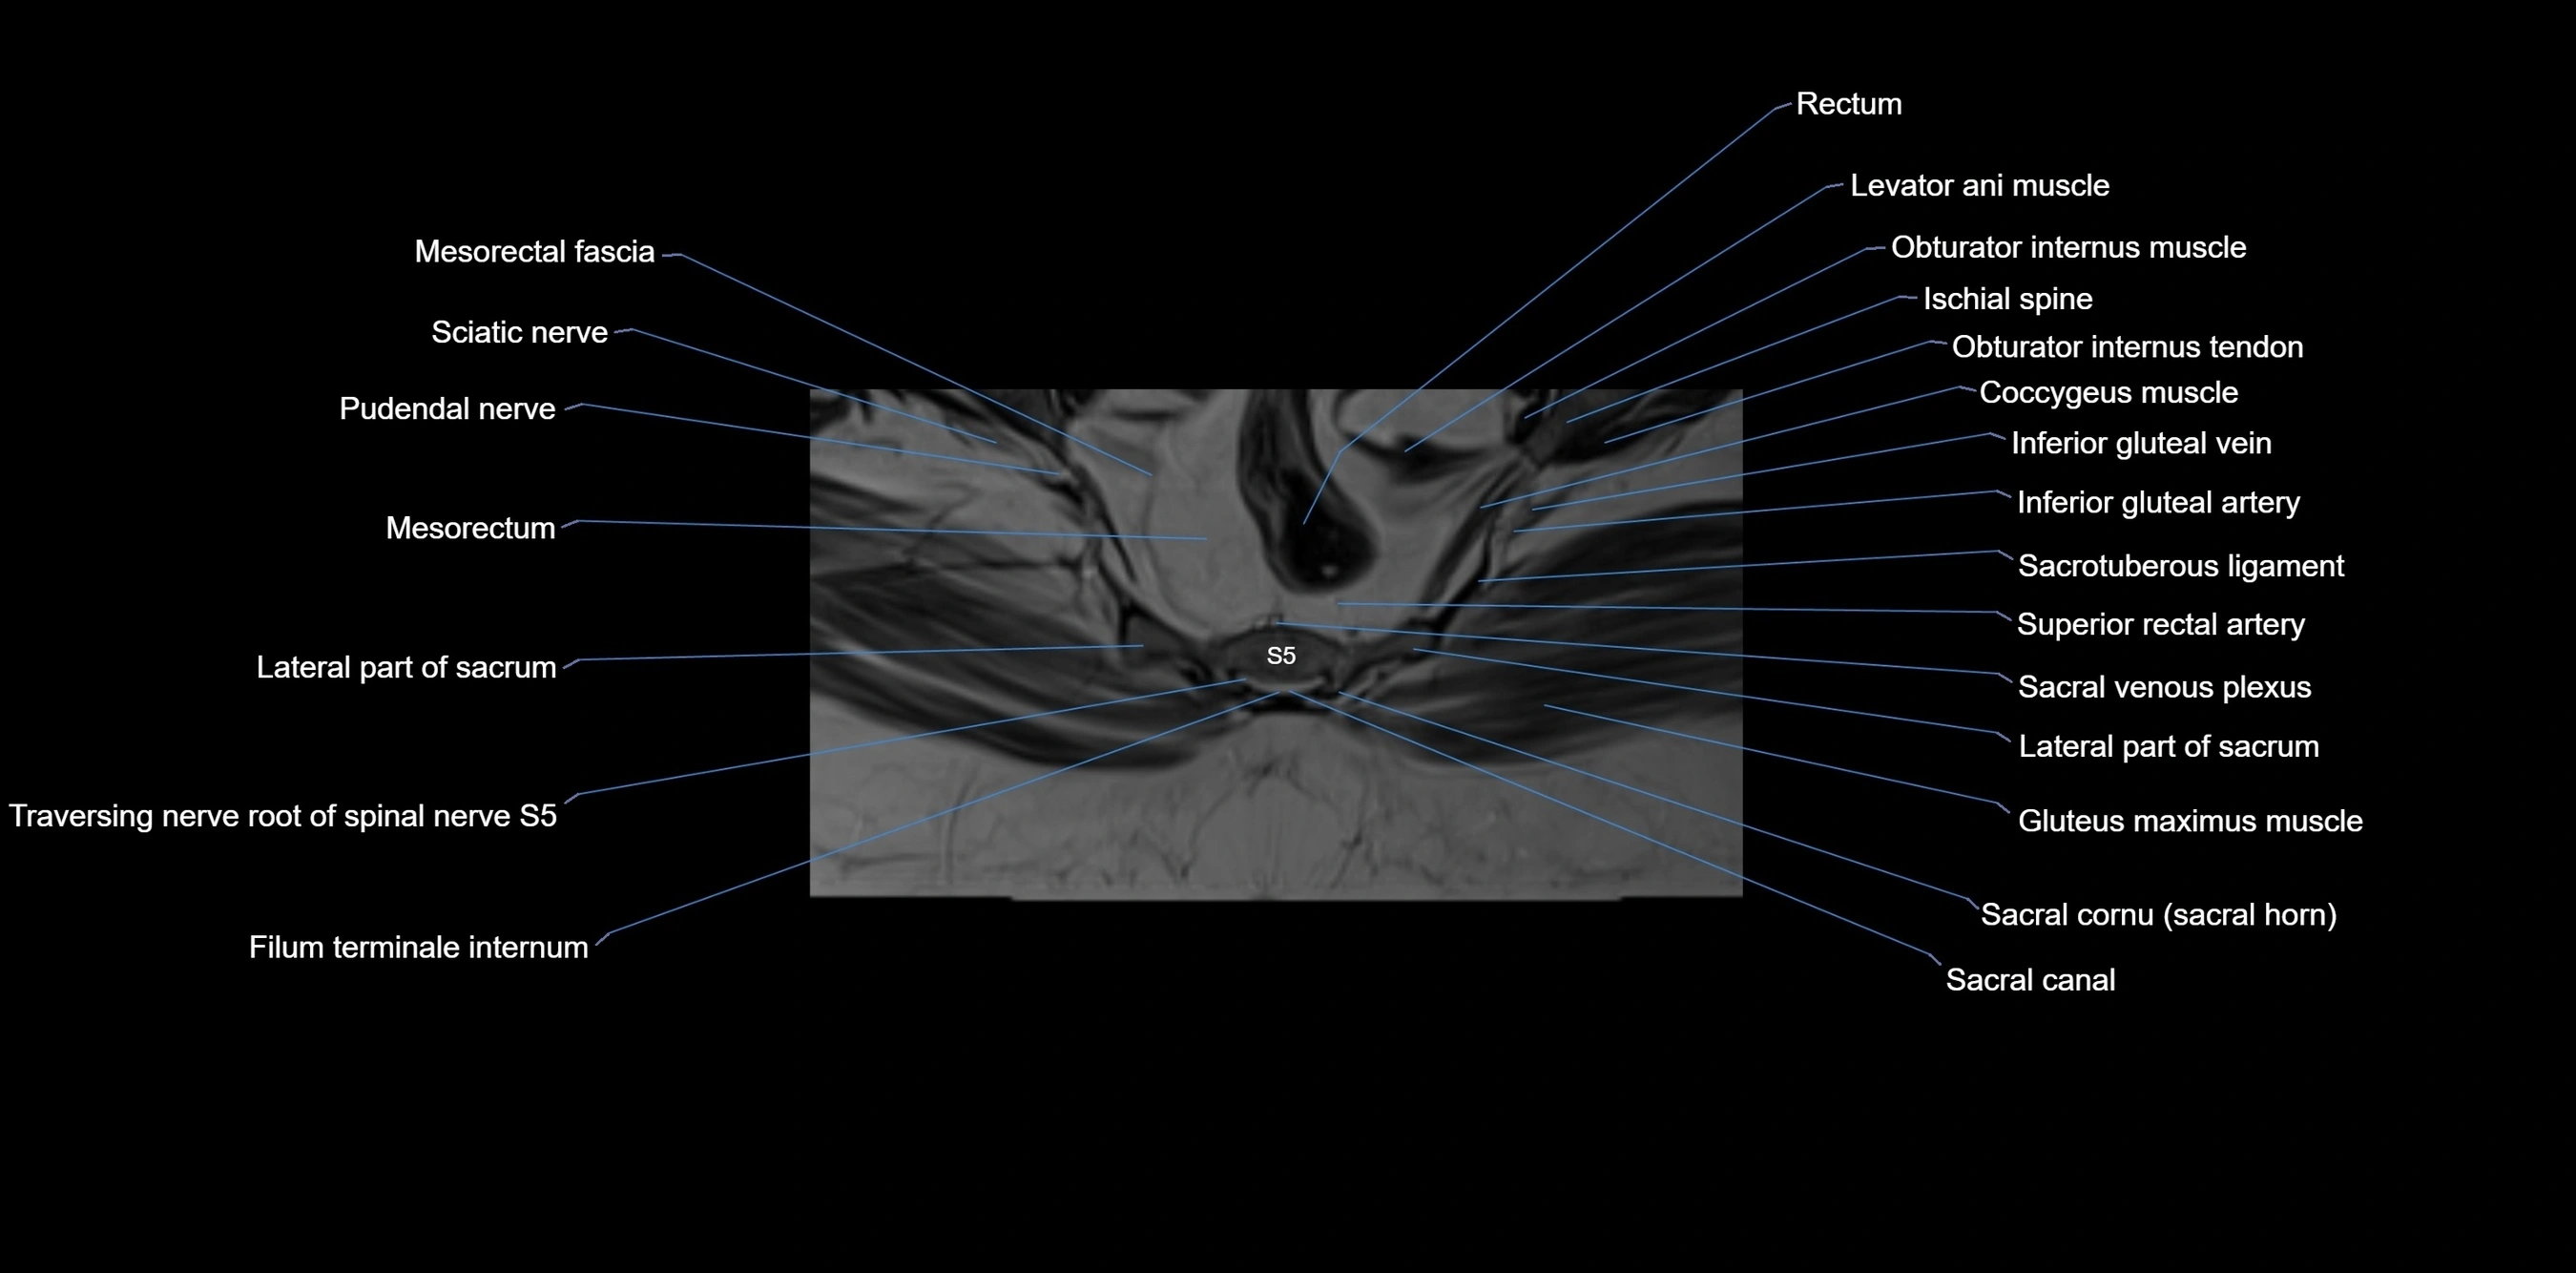

MRI image

image